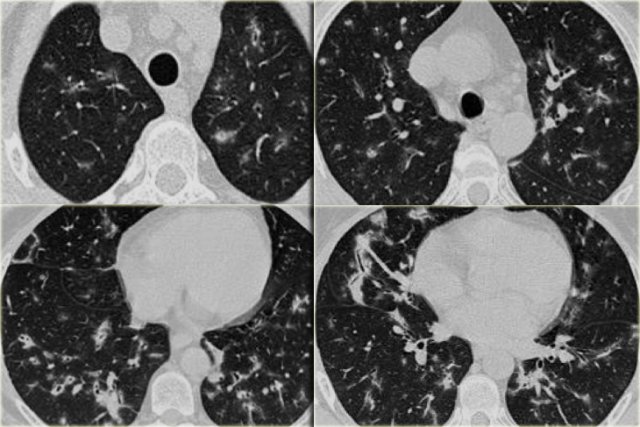

On the left some diseases with a nodular pattern.

- Hypersensitivity pneumonitis: ill defined centrilobular nodules.

- Miliary TB: random nodules of the same size.

- Sarcoidosis: nodules with perilymphatic distribution, along fissures, adenopathy.

- Hypersensitivity pneumonitis: centrilobular nodules, notice sparing of the subpleural area.

- TB: Tree-in-bud appearance in a patient with active TB.

- Langerhans cell histiocytosis: early nodular stage before the typical cysts appear.

- Respiratory bronchiolitis: ill defined centrilobular nodules of ground-glass opacity.